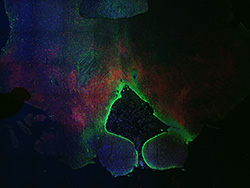

Merged

6PCW human midbrain